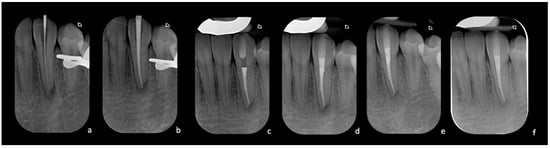

Template Production

The STL file of the optical intraoral scan and the DICOM data of the CBCT were exported in a specific software (Geomatic) for the definition of the target. A template was modeled as a skeleton of a removable partial prosthesis, printed in titanium using an additive manufacturing process with an SLM (Selective Laser Melting My Sint100 Sisma) with Grade 23 medical titanium. When the template was printed, the entire build platform was thermally treated in an oven (GLOW, Mihm-Vogt, Stutensee-Blankenloch, Germany) for heat relaxation. The 3D model of the patient derived from the optical impression was printed with a professional DLP printer (SOL LCD printer Ackuretta, Taipei City, Taiwan) in epoxy resin (ADORPRINT, Ador, Hilden, Germany). The 3D model was used to finalize the template (Figure 3). Once the template was made, the patient was scheduled for a second appointment.

After local anesthesia (Articaine Septanest with adrenaline 1:200,000; Septodont, Saint-Maur-des-Fosses, France), the operating field was isolated with a rubber dam. The correct positioning and stability of the guide were preliminary checked, and the temporary filling material was removed. Once the template was positioned, a 0.8 mm drill (210L16 205 008 Komet Dental Gear Brassier GmbH & Co. KG, Lemgo, Germany) was mounted on the blue ring contra-angle and inserted through the guide cylinder. Once the planned target point was reached, the scouting phase was performed by a K-File #10 instrument (Dentsply Sirona Endodontics, Ballaigues, Switzerland) (Figure 3). The electronic working length was measured using the electronic apex locator (Ai-Pex, Gullin WoodPecker Medical Instrument Co., Ltd., Guilin, China), and a periapical X-ray was performed to confirm the working length. The canal was shaped with rotary Ni-TI files (EdgeEndo Platinum, EdgeEndo, Albuquerque, NM, USA), and the apex was finished with an F3 file (Protaper Ultimate, Dentsply Sirona, Charlotte, NC, USA). Detersion was performed by multiple rinses of 5% sodium hypochlorite (Niclor 5—Ogna, Muggio dental division, MB—Italy). To seal the shaped canal, the single-cone technique with hydraulic cement (Endosequence BC Sealer, Brasseler USA Savannah, GA, USA) was used; the cavity was then provisionally sealed with temporary cement. After four days, the patient did not show any sign of inflammation and symptoms, and restoration was then performed with adhesive (Optioned SoloTM Plus, Kerr Corporation, Orange, CA, USA) and a composite technique (Enamel plus, HFO Micerium, Rosbach, Germany). A final radiograph was performed at the end of the restorative procedures (Figure 4).

Figure 3. (a) Titanium template packaged and placed on the 3D-printed model: buccal view, (c) lingual view. (b) Three-dimensional simulation of the drill’s path in relation to the bio-model and the template: buccal view, (d) lingual view. (e) Intra-operative image of the K-file was inserted immediately after locating the canal. (f) The printed titanium template: the access cylinder can be customized entirely (in diameter and height). (g) Intra-operative image with the template correctly positioned.